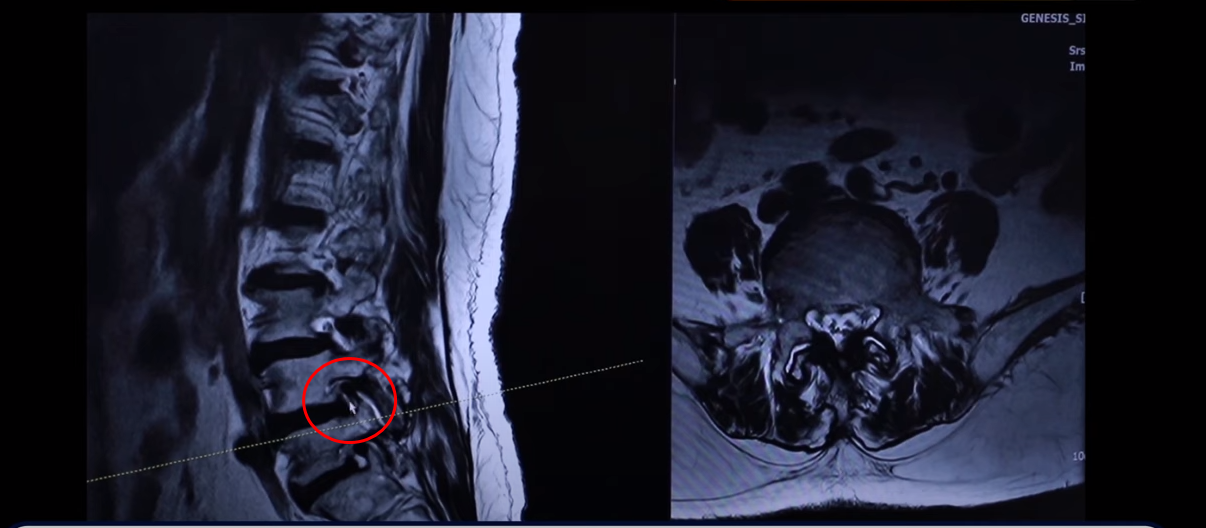

그런데 특히 이 아랫마디 가보면 여기가 많이 좁아져 있습니다. 특히 뭐가 문제냐면 이 척추관보다는 여기 추간공을 보면 이렇게 좁아져 있습니다. 다른 데하고 굉장히 크게 차이가 많이 나죠.

이제 이렇게 환자들이 이런 걸 보시면 아예 까맣게 변해 있다. 신경이 많이 눌리니까 이게 왼쪽 다리로 가는 신경입니다. 그 다음에 오른쪽 다리로 가는 신경을 보면 신경이 여기 지금 까맣게 보입니다. 이 지방이 다 없어져버린 겁니다. 신경 공간이 좁아져 있죠.

그 다음에 이거는 디스크고 이 뒤에 있는 건 황색인대입니다. 이것들이 지금 두꺼워져 있기 때문에 여기 공간이 좁아지는 겁니다. 그래서 이제 오른쪽 다리, 왼쪽 다리가 다 신경이 눌리고 아파서 못 걷는 분입니다.

그러면 이런 분들은 뭐라고 얘기를 듣냐면 수술을 하는데 여러 마디가 안 좋다 보니, 가령 이 마디는 전방 전위가 있고 이 마디는 심하게 양쪽 다리로 가는 양쪽 신경 구멍들이 좁아져 있는 거죠. 그러면 여러 마디 수술을 해야 되는데 또 전방전위도 있기 때문에 나사를 박는 수술을 해야 된다고 듣는 경우가 많습니다.

나사를 많이 박게 되면 수술의 효과는 일반적으로 한마디 하는 것보다는 더 떨어지게 돼 있습니다. 그래서 이분이 병원에 묻습니다. 수술하면 좋아질 수 있느냐 근데 이제 시원하게 좋아진다는 대답을 안 하는 겁니다. 그래서 이분이 수술을 포기하고 저희 병원에 오셨는데 그러면 이렇게 신경이 눌려 있는데 어떻게 수술하지 않고 치료를 할 수 있느냐 그게 저희가 계속 설명하고 있는 부분입니다.